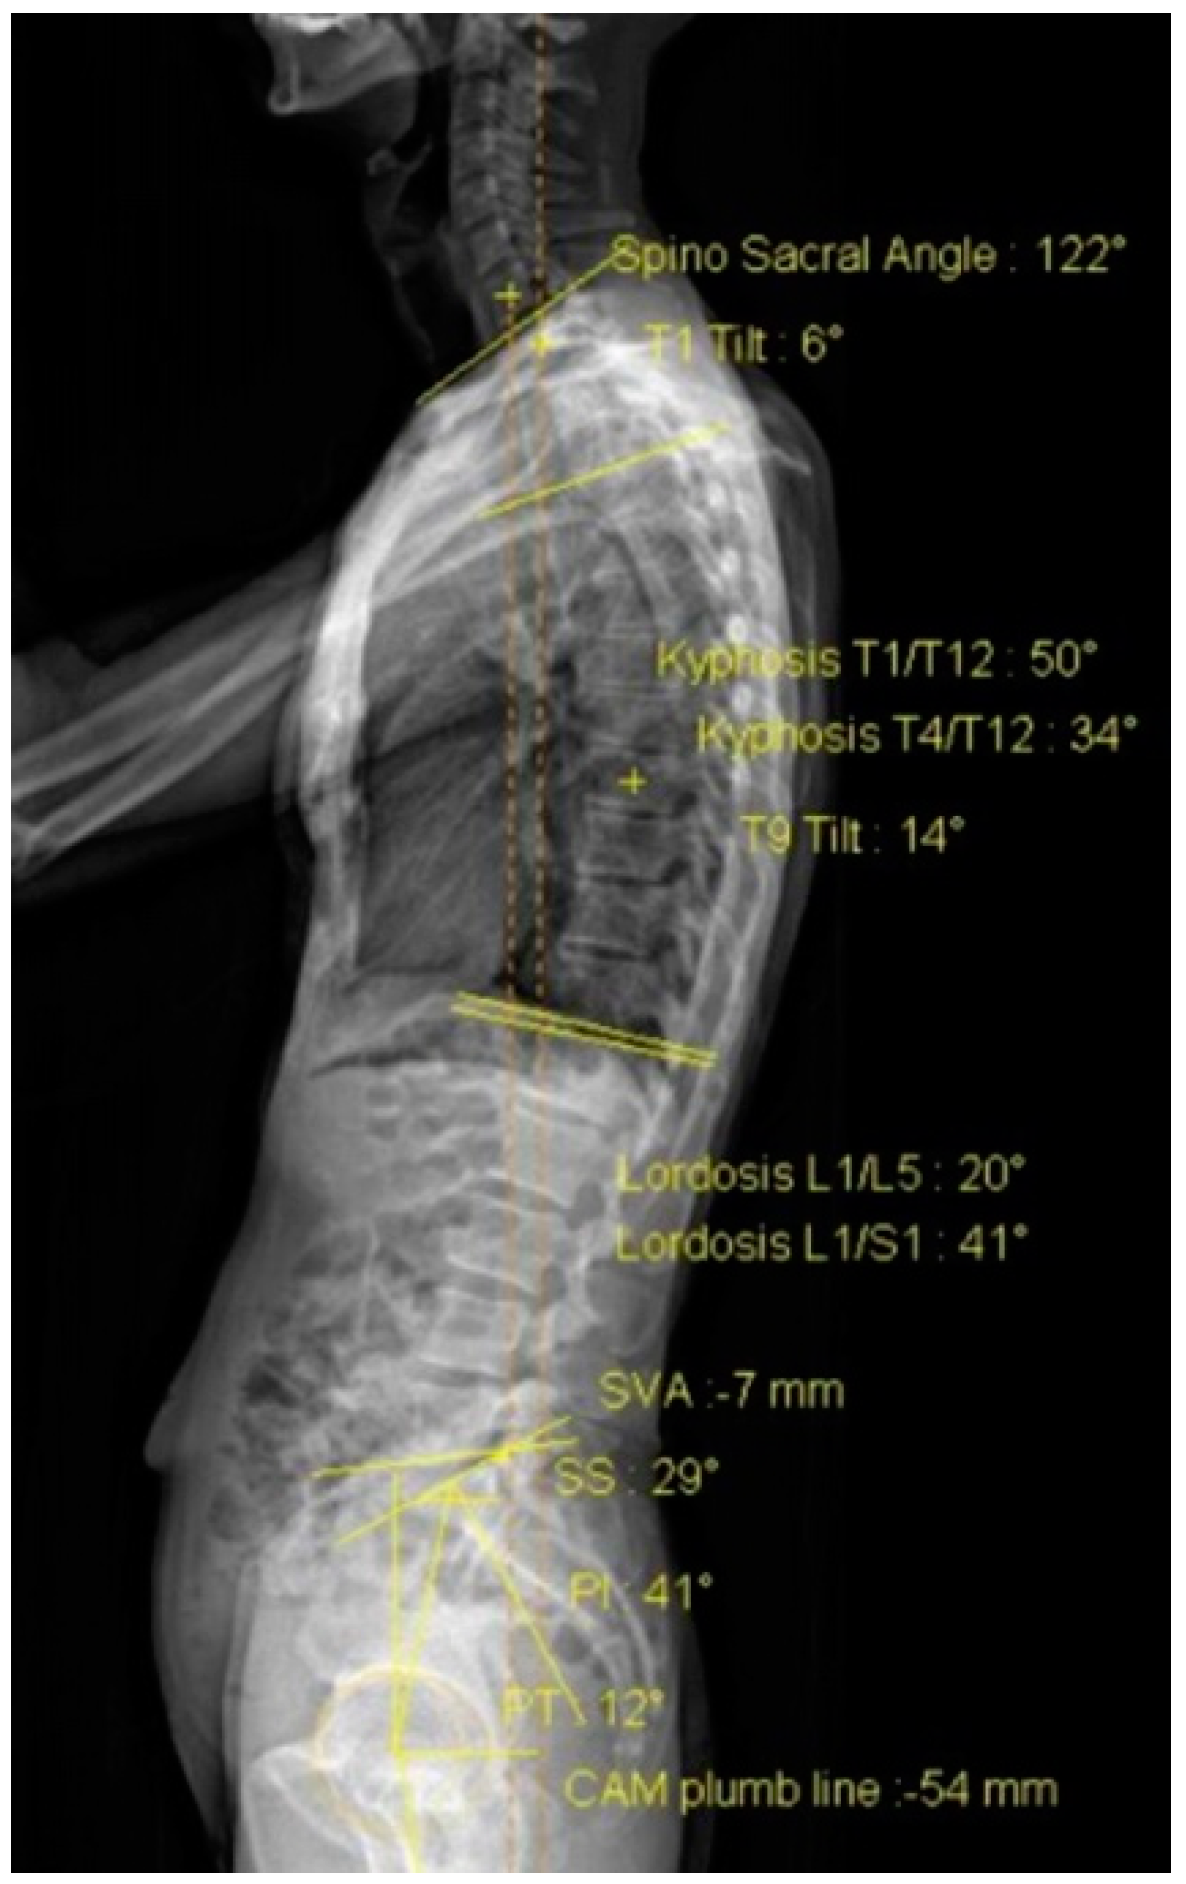

| Sagittal alignment | |||||

| T1/T12 kyphosis (°) | 44.31 ± 9.80 | 44.42 ± 10.03 | −0.12 | 0.891 | 0.03 |

| L1/L5 lordosis (°) | 26.04 ± 14.99 | 25.54 ± 14.79 | 0.50 | 0.383 | 0.17 |

| Pelvic incidence (°) | 48.50 ± 12.05 | 48.04 ± 12.07 | 0.46 | 0.474 | 0.14 |

| Sacral slope (°) | 31.27 ± 9.41 | 31.31 ± 9.37 | −0.04 | 0.952 | 0.12 |

| Pelvic tilt (°) | 17.12 ± 8.09 | 16.81 ± 8.34 | 0.31 | 0.415 | 0.16 |

| Sagittal vertical axis (mm) | 36.04 ± 27.06 | 40.38 ± 26.10 | −4.35 | 0.204 | 0.26 |